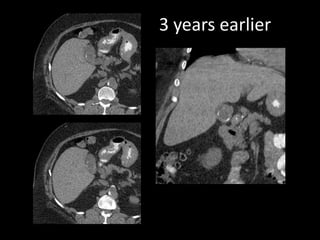

This document describes four patient cases seen by different doctors, including a 72-year-old female with abdominal pain, a 42-year-old female with abdominal pain and bloody diarrhea, a 37-year-old male with chest pain and vomiting of digested blood, and a 67-year-old male with an abnormal heart ultrasound.